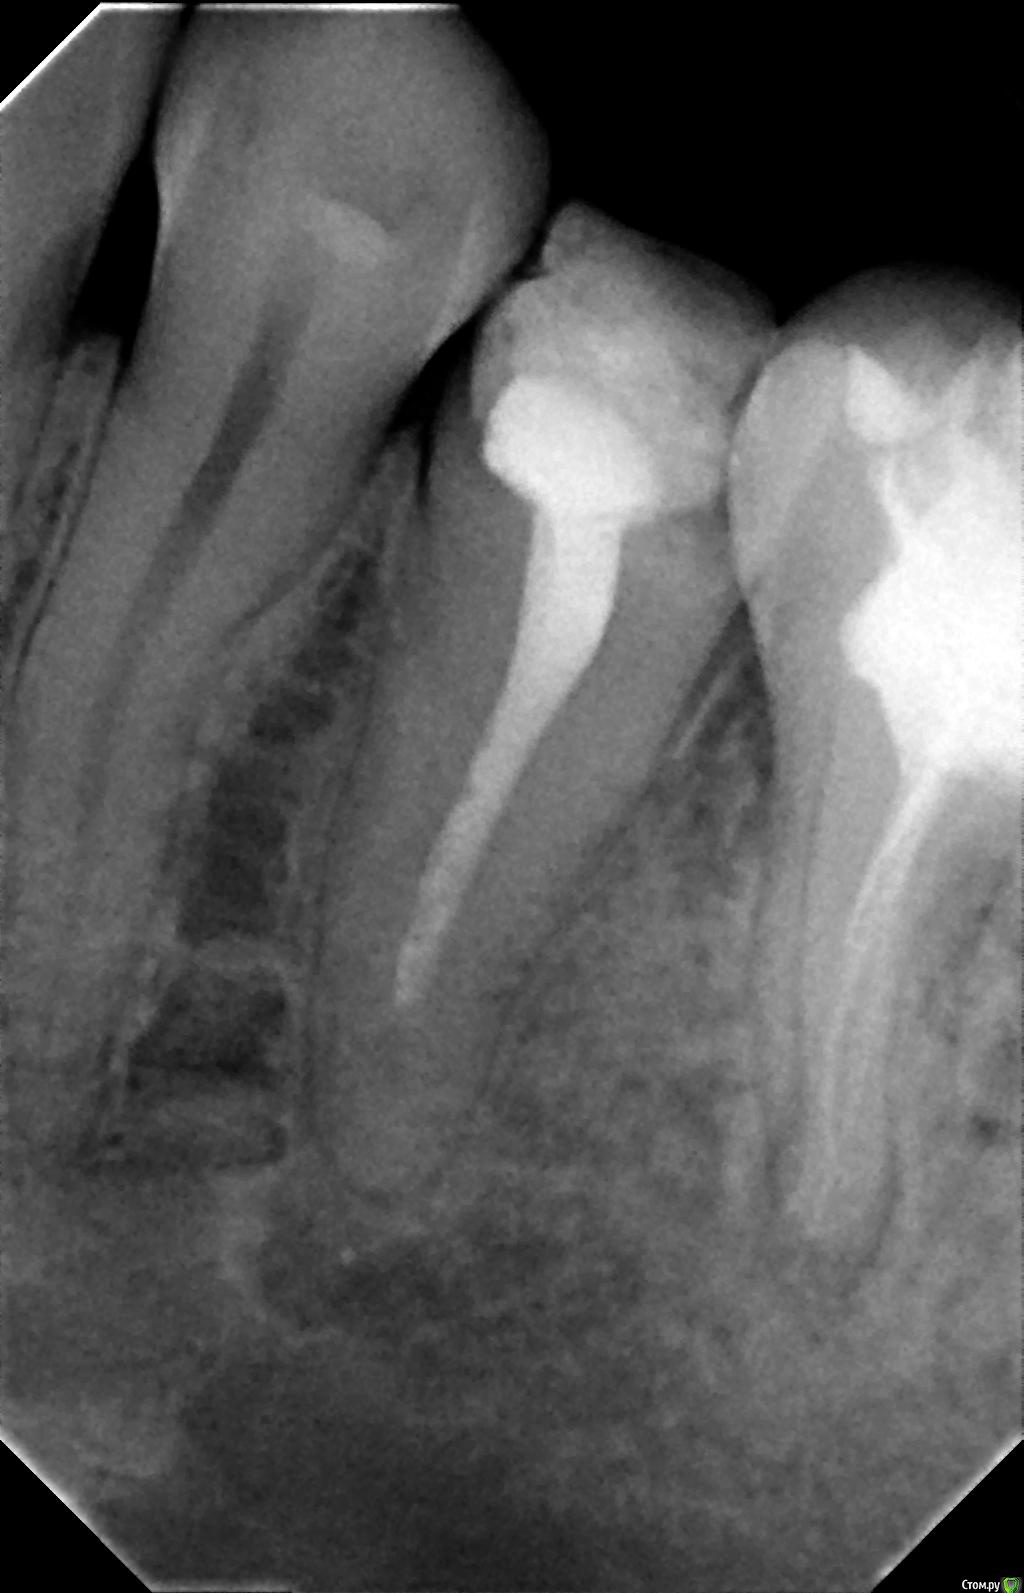

Ёлкаа Опубликовано 8 февраля, 2016 Поделиться Опубликовано 8 февраля, 2016 Добрый день!Помогите, пожалуйста, совсем не знаю, что мне делать.На "мертвом" зубе образовалась киста. В основном врачи рекомендуют удалить зуб.Подскажите, пожалуйста, есть ли возможность сохранить зуб или в этом нет смысла. Фото 5-ки, 6-ки и 7-ки прилагаю.Также в дальнейшем в планах ставить брекеты.Помогите, я совсем запуталась Заранее спасибо! Ссылка на комментарий

DmitrySH Опубликовано 9 февраля, 2016 Поделиться Опубликовано 9 февраля, 2016 Не уверена, что прибегну к лечению, т.к. оно очень дорогостоящее и длительное, а я планирую беременность и в дальнейшем брекеты, а т.к. у меня скученность зубов возможно все равно придется удалять что-то. Да не такое уж и длительное лечение. Примерно 3 визита на 1 зуб. А постоянные лабораторные реставрации лучше уже после ортодонтического лечения, раз планируется. По ортодонтическим показаниям 6 и 7 зубы обычно не удаляются. Это участь 4-5 1 Ссылка на комментарий

Ёлкаа Опубликовано 7 марта, 2016 Автор Поделиться Опубликовано 7 марта, 2016 В выходные приступила к лечению кисты.Мне распломбировали каналы, обработали их метапастой с кальцием (каласепт) и поставили временную пломбу.Теперь через 2 недели осмотр. 1 Ссылка на комментарий